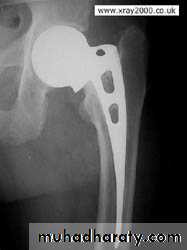

ELDERLY PEOPLE

5.Austen Moore.

6.Total hip replacement.